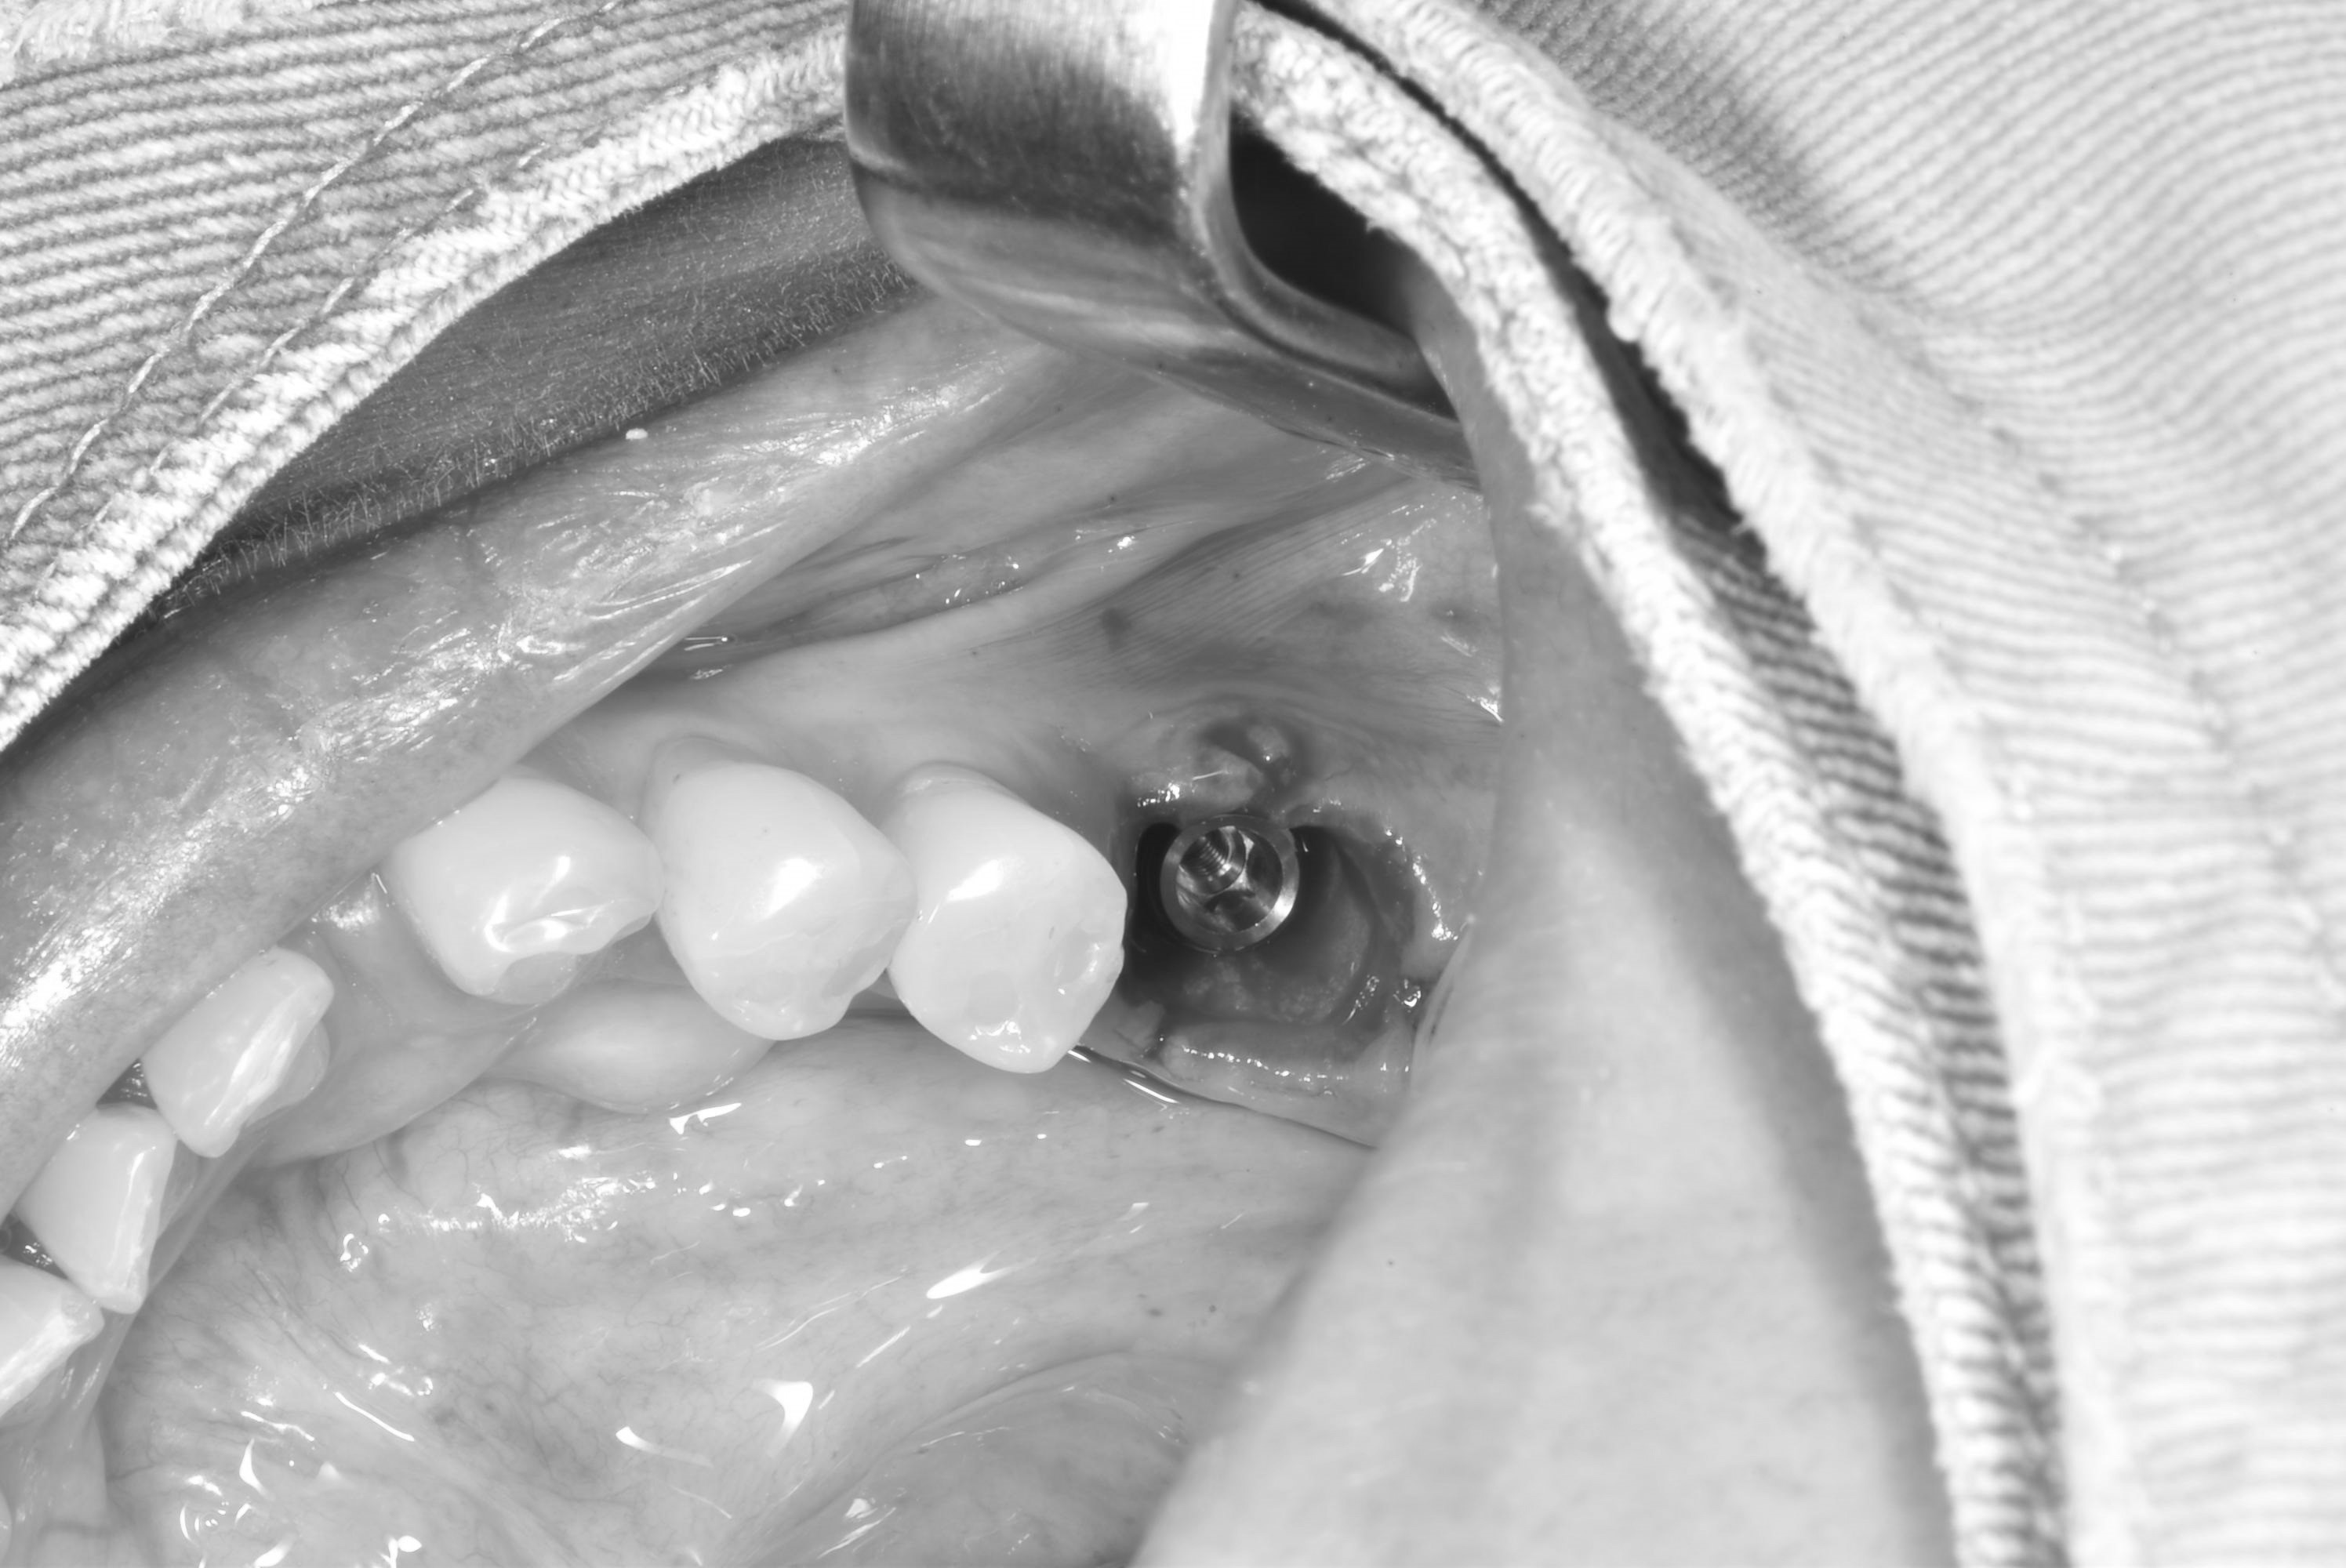

案例五

立即拔除牙根不好的牙齒

醫生透過電腦斷層評估骨頭狀況決定植入的植體所放的寬度與深度

2-3月癒合,取下癒合螺帽,透過數位口掃至技公所製作假牙

2-3個月癒合,7-10天完成假牙 ,試戴、調整咬合高度並鎖上,封填,完成